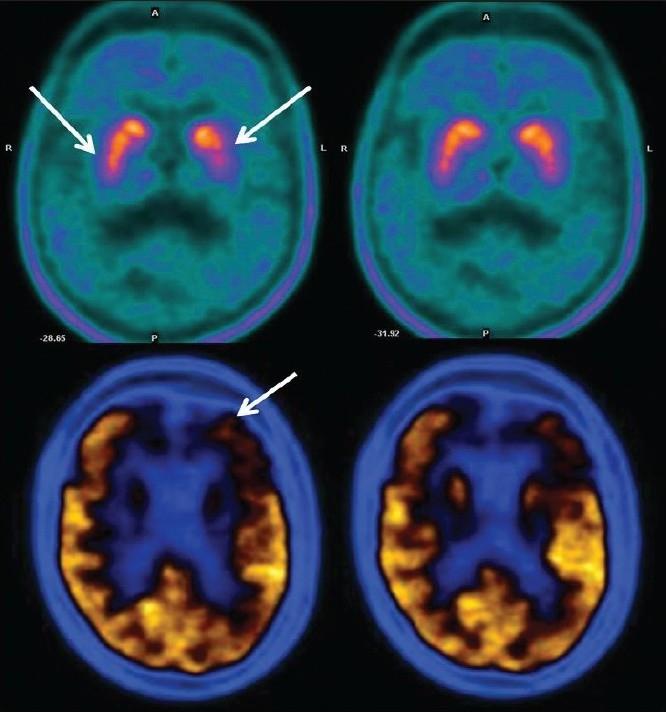

In the patient population included in our study group 36 were normal, 39 had MCI, 40 had AD, 14 had FTD, and 13 had DLBD and 11 dementia due to other miscellaneous causes. MCI patients showed primarily reduced tracer uptake in the mesio-temporal cortex. AD patients showed reduced tracer concentration in temporo-parietal lobes, while patients with advanced diseases showed frontal lobe disease additionally. In subjects of FTD, reduced radiotracer uptake in the fronto-temporal lobes was noted. In addition, FTD patients also showed basal ganglia defects. In contrast the DLBD patients showed globally reduced FDG uptake including severely affecting the occipital cortices.

在我们研究组纳入的患者群体中,36人正常,39人患有MCI,40人患有AD,14人患有FTD,13人患有DLBD,11人因其他各类病因患有痴呆。MCI患者主要表现为内侧颞叶皮质示踪剂摄取减少。AD患者颞顶叶示踪剂浓度降低,而晚期疾病患者还表现出额叶病变。在FTD受试者中,额颞叶放射性示踪剂摄取减少。此外,FTD患者还表现出基底神经节缺陷。相比之下,DLBD患者表现为FDG摄取整体减少,包括严重影响枕叶皮质。